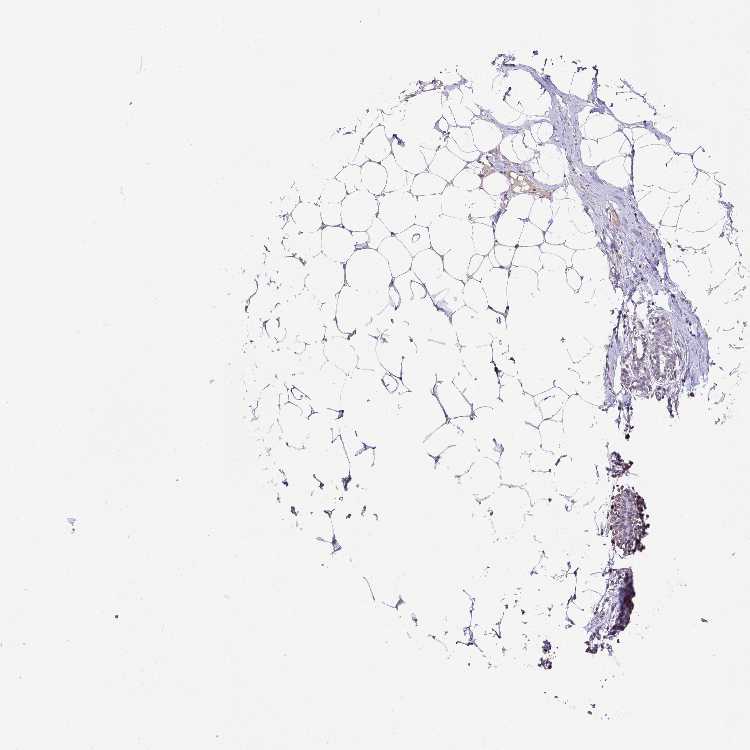

BREAST - Antibody stainingi

Antibody staining in the annotated cell types in the current human tissue is reported as not detected, low, medium, or high, based on conventional immunohistochemistry profiling in selected tissues. This score is based on the combination of the staining intensity and fraction of stained cells.

Each image is clickable and will lead to virtual microscopy that enables deeper exploration of all samples and also displays staining intensity scores, fraction scores and subcellular localization as well as patient and tissue information for each sample.

Antibody HPA041725Antibody CAB032866

Adipocytes Not detectedNot detected

Glandular cells Not detectedNot detected

Myoepithelial cells LowNot detected